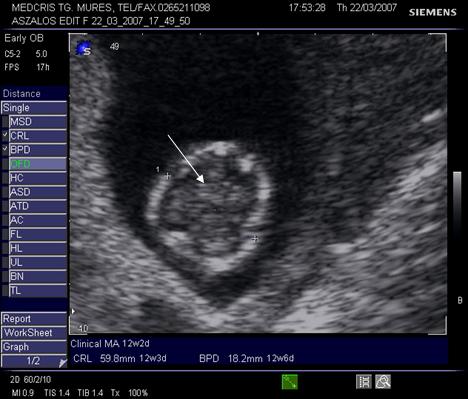

Fig. nr. 28.

Sectiune transversala prin craniul fetal, la 12 sapt se remarca simetria

plexurilor choroide, viitoare emisfere cerebrale